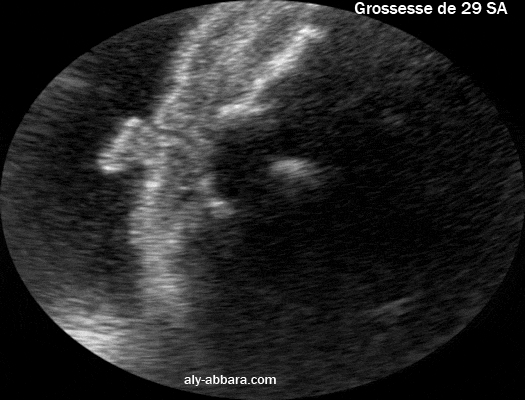

Une coupe échographique céphalique coronale montrant une partie de du pavillon de l'oreille externe et le conduit auditif externe.

fœtus âgé de 29 SA